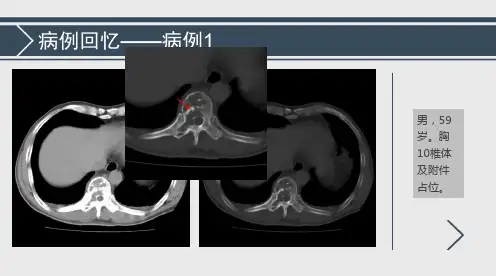

本文报道了我科于2005年至2010年间,经住院手术或病理活检共收治确诊的sp病例9例,其中胸椎1例、骶骨3例、髂骨3例、额顶叶1例以及脾脏1例。

发生于胸椎1例,髂骨3例,骶骨3例,额顶叶1例,脾脏1例。

所有病例均行x线,ct以及mr检查。